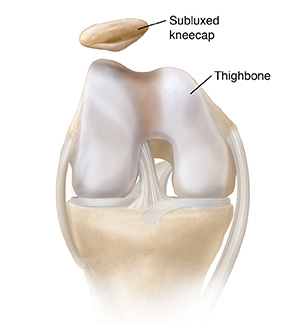

Dislocation

Sometimes a muscle or ligament in the knee is pulled the wrong way. Or the kneecap may be pushed too hard. Then the kneecap may move partly out of the groove (subluxation). It may even move completely out (dislocation).